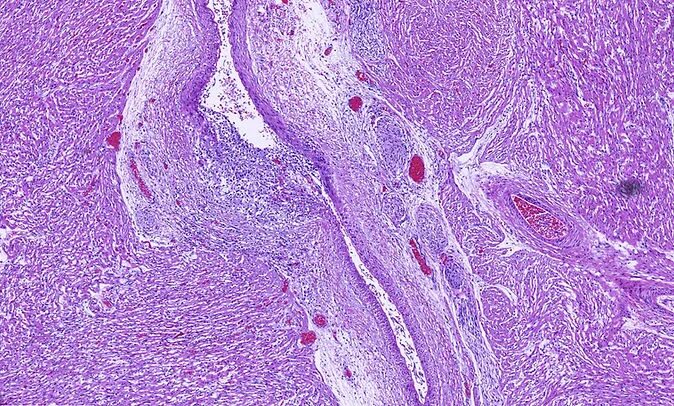

Гистология миомы